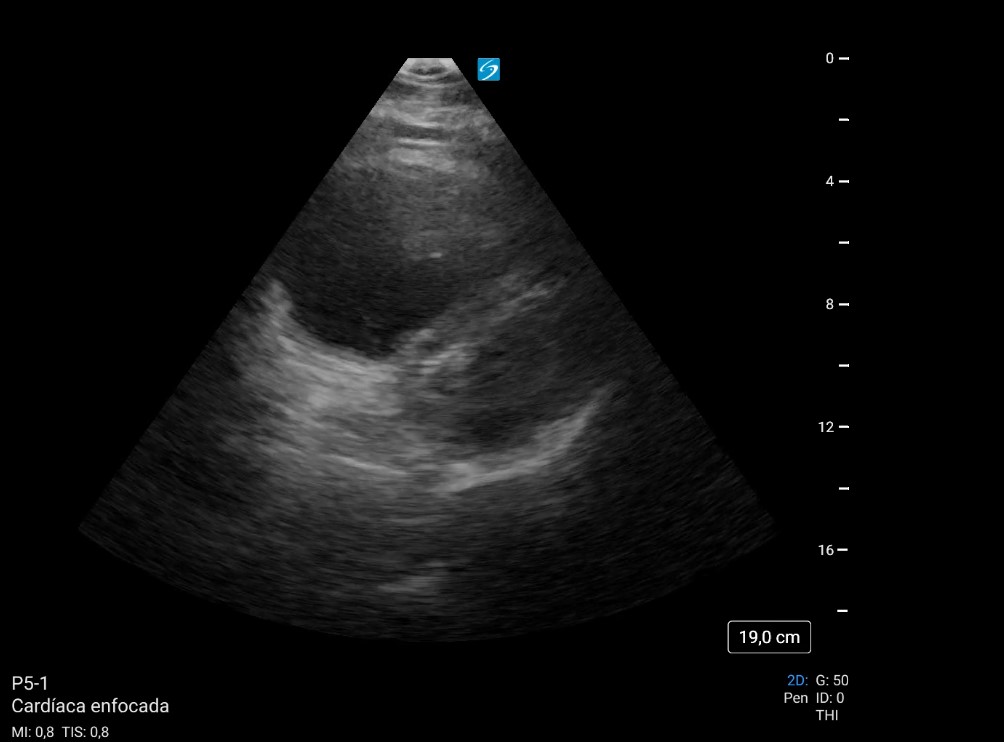

Se decide realizar ecocardiografía clínica para valorar las cavidades cardíacas, observando datos de sobrecarga derecha y una imagen compatible con trombo en ventrículo derecho: signos indirectos de TEP, confirmando alta sospecha, iniciando anticoagulación y solicitando angioTC directamente.

El angioTC pulmonar solicitado confirmó nuestra sospecha: TEP bilateral, proximal y distal, con signos de hipertensión pulmonar y sobrecarga cardíaca derecha. Posteriormente, ingresó en Medicina Intensiva, donde se confirmaron la presencia de trombo intraventricular de 7-8 cm y la TVP poplítea. Se continuó con anticoagulación y el paciente evolucionó favorablemente.